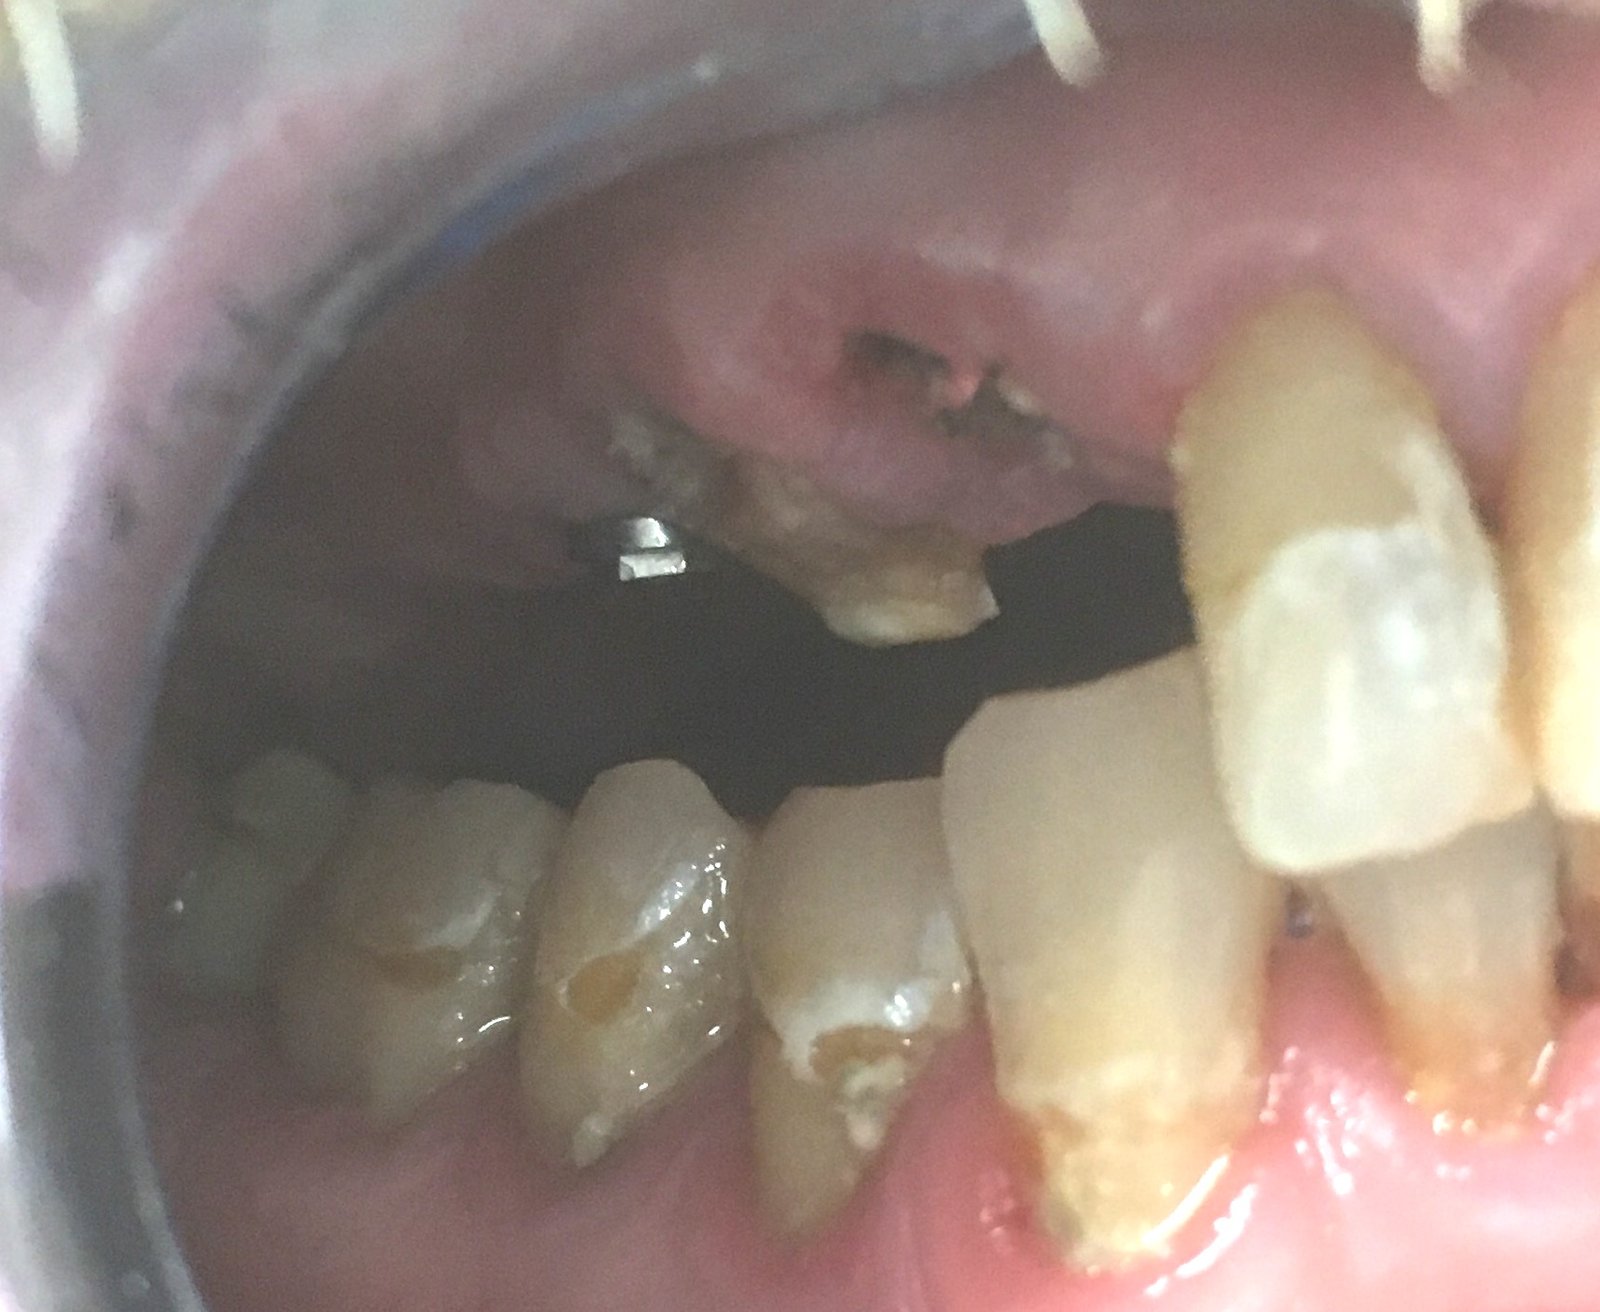

Los implantes de 17 y 27

Buenos días Paciente que acude a consulta con fracaso de implantes a la altura de 15-13 y 22. Los Implante de 17 y 27 los podemos conservar, pero no tenemos [...]